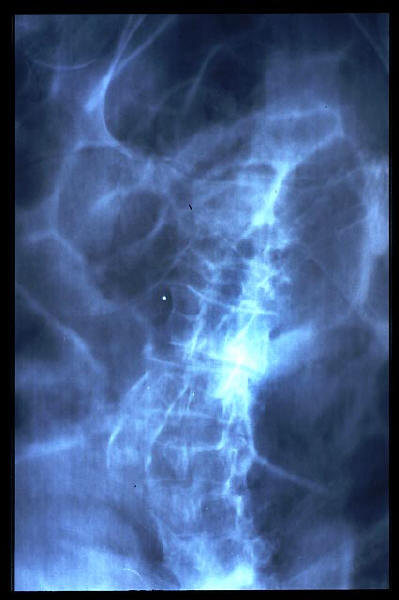

Escoliosis. Espondilolistesis.